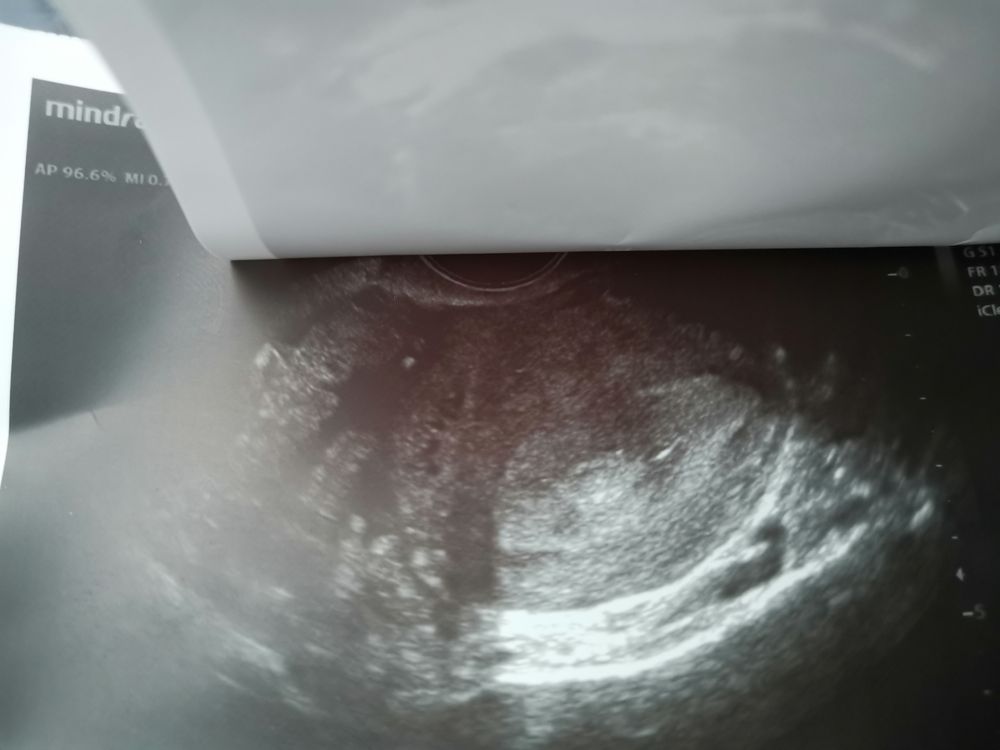

Я реву!Полип?

Мой организм не хочет беременеть На узи хожу раз в три месяца , были 2 маленькие миомы , сказали зачатию не мешают. Сегодня сходила на узи , а у меня полип . Вот откуда он ? Узист сказала прийти сразу после месячных , может уйти . Кто разбирается , фото скину . может это не полип? 😭😭😭

Если это же полип, то после месячных ничего не изменится. На какой день цикла делали УЗИ?

Бабенко Яна, такие диагнозы ставятся только при УЗИ в начале цикла, т.к. под конец цикла эндометрий начинает отслаивается и полная картина не ясна. Поэтому не расстраивайтесь, для начала переделайте УЗИ. Миомы очень маленькие, на зачатие не влияют.